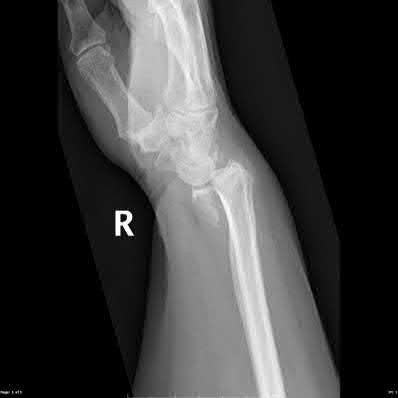

Question 6

A 22-year-old male falls onto an outstretched hand and sustains a displaced fracture through the proximal pole of the scaphoid. Avascular necrosis of the proximal pole is highly likely due to the disruption of its primary vascular supply. Which vessel provides this critical retrograde perfusion?

Explanation

The primary blood supply to the scaphoid is from the dorsal carpal branch of the radial artery, which enters the dorsal ridge of the scaphoid at the waist and courses proximally. This retrograde blood flow makes proximal pole fractures highly susceptible to avascular necrosis and nonunion. The superficial palmar branch provides a minor supply (about 20%) to the distal pole.